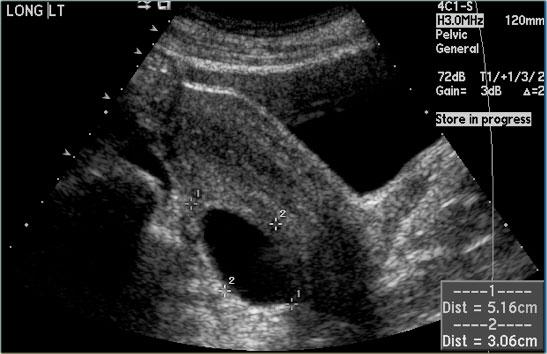

Hình ảnh siêu âm cho thấy hai nang đơn giản ở buồng trứng phải với mô đệm buồng trứng ở giữa.

Các mạch máu xung quanh bình thường và không có vách ngăn có mạch máu.

Đây là các nang nang trứng đơn giản ở phụ nữ tiền mãn kinh.